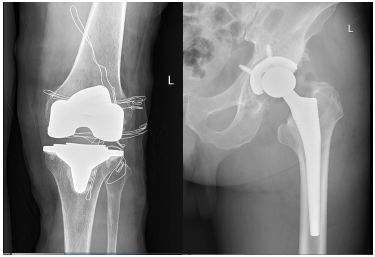

动静记者今天从贵州医科大学附属医院了解到,国家集采后的人工关节类骨科耗材目前已在该院手术中使用。髋关节平均价格从4万元下降至7000元左右,最高中选价为9920元,最低中选价为1788元;膝关节平均价格从5万元下降至5000元左右,最高中选价为6877元,最低中选价为2468元。

据了解,2021年底,国家医保将人工髋关节、人工膝关节纳入国家组织第二批高值医用耗材集采范围。集采后,人工髋关节、人工膝关节平均价格下降82%,患者负担大幅减轻。

人工关节置换手术是治疗因外伤、运动损伤、退变老化等原因导致的股骨头坏死、关节损伤、骨性关节炎等疾病的有效手段之一,能够极大程度恢复患者关节活动功能,提高患者生活质量。由于骨科耗材技术分类和组合复杂,因此集采前的人工关节价格较高,在骨科手术的医疗总费用中占比较大。

据悉,此次人工关节带量采购周期为2年,中选产品以含伴随服务费的中选价格为支付标准,不设首先自付比例,全额纳入医保支付。这也是继药品、冠脉支架后,人工关节类骨科耗材集采的成功开标。

据统计,贵州医科大学附属医院骨科自4月22日正式采用国家集采关节置换假体至今,已开展集采假体关节置换手术髋关节25台、膝关节39台。